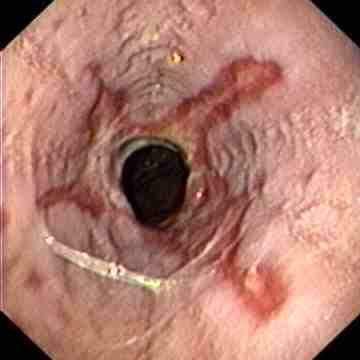

Reflux oesophagitis grade C-D according to the Los Angeles classification